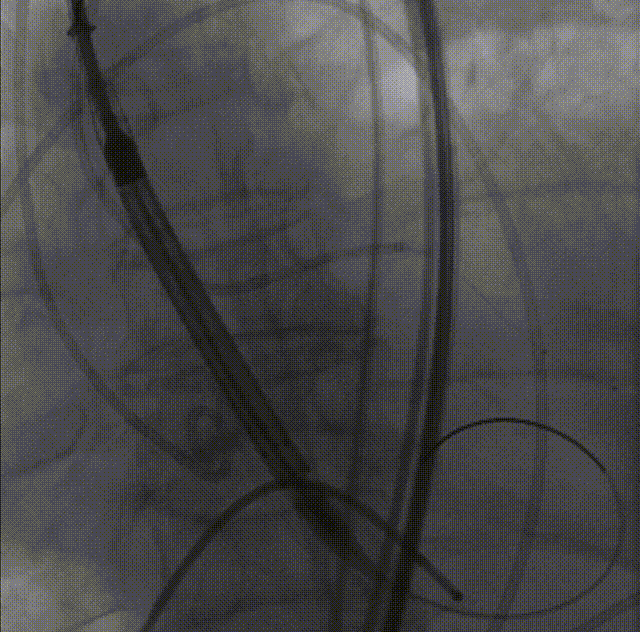

LM烟囱支架植入4.0*30mm